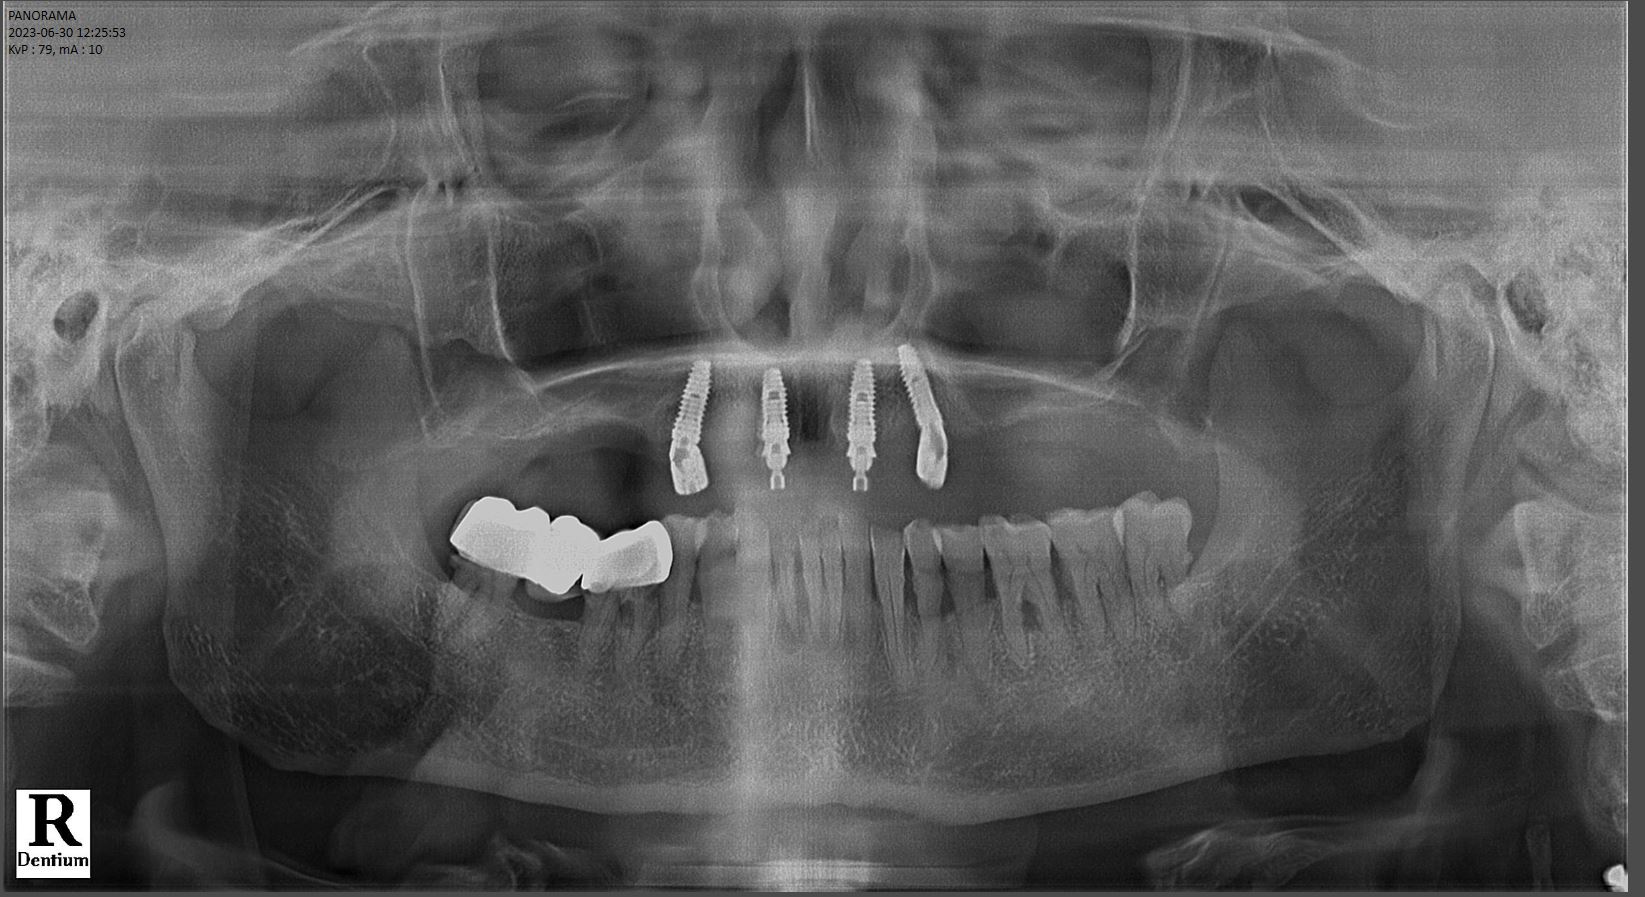

“Do mất toàn bộ răng hàm trên nên phần môi của chú bị lép sâu khiến cho gương mặt mất thẩm mỹ. Mô lợi bị chai sần, có nhiều vết tì đè do sử dụng hàm giả tháo lắp nhiều năm. Dù vùng xương hàm bị tiêu đi khá nhiều, tuy nhiên may mắn cho chú là xương ở vùng răng số 5 đổ lại vẫn còn tương đối tốt, phù hợp để chúng tôi đặt 4 trụ implant và phục hình 12 răng cho chú”, bác sĩ Dương phân tích.

Hình ảnh phim X-quang sau cấy ghép implant toàn hàm All on 4 của khách hàng Doãn Văn Chinh (Ảnh: Lạc Việt Intech)